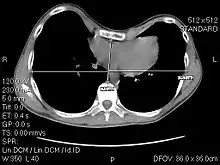

The Haller index, created in 1987 by J. Alex Haller, S. S. Kramer, and S. A. Lietman,[1] is a mathematical relationship that exists in a human chest section observed with a CT scan. It is defined as the ratio of the transverse diameter (the horizontal distance of the inside of the ribcage) and the anteroposterior diameter (the shortest distance between the vertebrae and sternum).[2]

- distance 1 is the distance of the inside ribcage (at the level of maximum deformity or at the lower third of the sternum)

- distance 2 is the distance between the sternal notch and vertebrae.

A normal Haller index should be about 2.5. Chest wall deformities such as pectus excavatum can cause the sternum to invert, thus increasing the index.[6][7] In severe asymetric cases, where the sternum dips below the level of the vertebra, the index can be a negative value.[8]